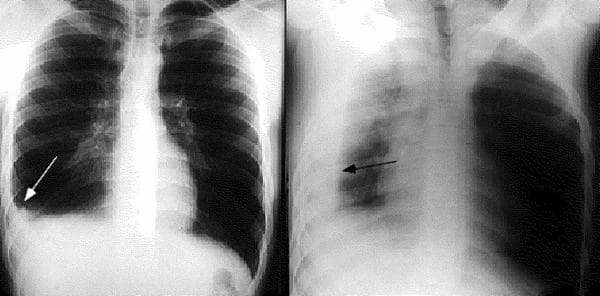

Tràn dịch màng phổi là tình trạng lượng dịch tích tụ trong khoang trống giữa phổi và thành ngực quá nhiều và tách phổi ra khỏi thành ngực. Tình trạng này kéo dài có thể gây khó khăn khi thở, nguy hiểm hơn là có thể gây tử vong. Vậy điều trị tràn dịch màng phổi như thế nào?

Tràn dịch màng phổi là tình trạng lượng dịch tích tụ trong khoang trống giữa phổi và thành ngực quá nhiều